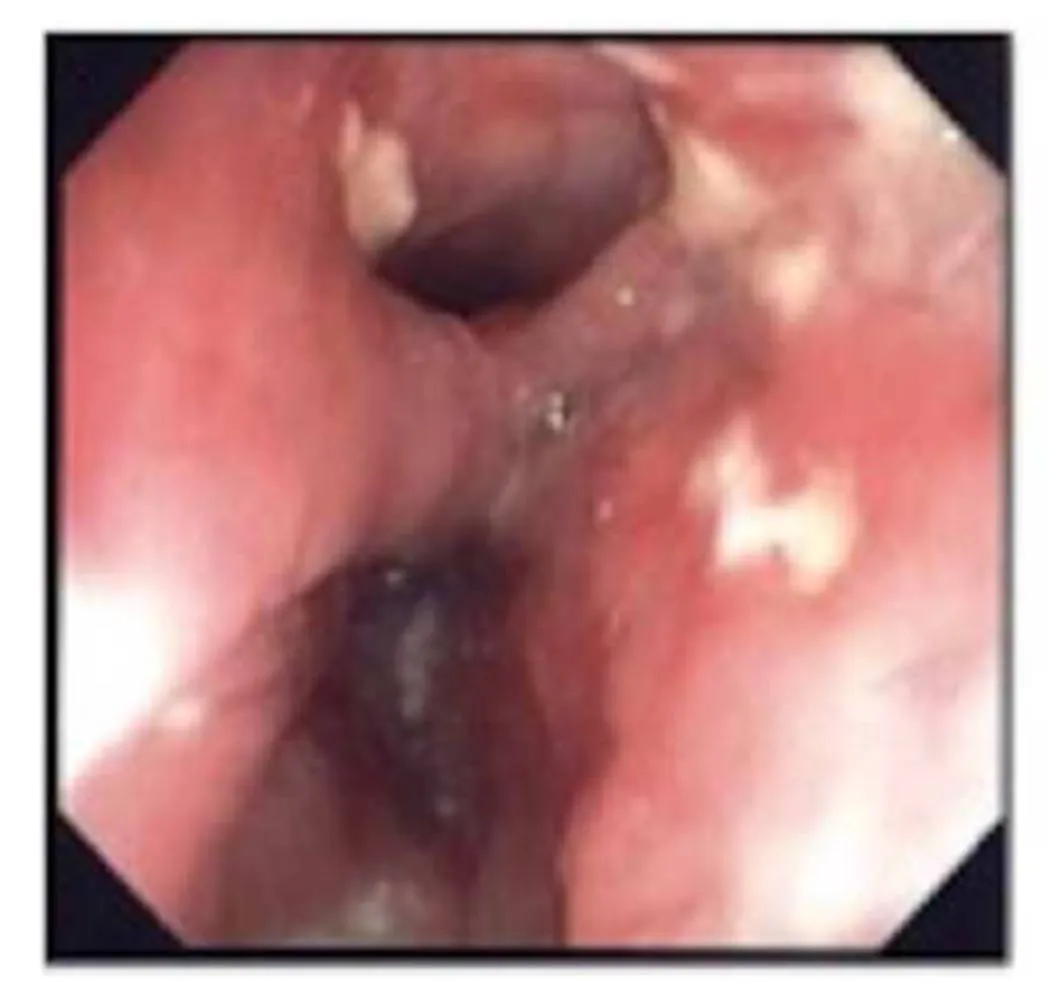

At the Department of Thoracic Surgery an EGD was performed under general anaesthesia. Flexible endoscopy demonstrated a megaesophagus with a diameter of 8-10 cm 20 cm from the incisors and a second lumen 5 cm more distal (Fig. 2).

Figure 2: Photodocumentation from the esophagoscopy, photo taken at the same level as the upper arrow in Fig. 1

The photo demonstrates the neck of the diverticulum in the distal part of esophagus.

The lower lumen is the esophagus and the upper lumen is the diverticulum.